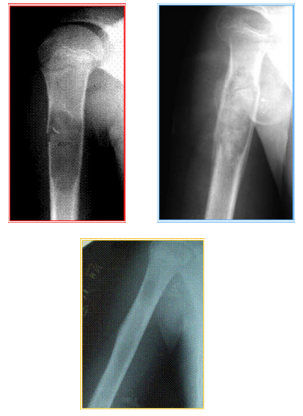

The unique feature of the LitAr material is the stimulation of slightly differentiated stem cells in-vivo which, at the time of LitAr’s material development, was not attained by anyone in the world.5 www.Lit-Ar.ru presents details of key differences between LitAr and its foreign analogs. Clinical testing which validated utility of Dr. Litvinov’s technology were carried out by Prof. Vladimir Belokonev, Dr. Alexander Kosulin, a cranioplasty surgeon and Dr. Oleg Nikiforov, a thoracic surgeon. In 1994, the first operation was successfully conducted by Dr. Michail Babkov, assistant professor under the Prof. Alexander Krasnov direction. Figure 3 demonstrates the Litar application in the restored bone tissue. Another consequences of this fracture, such as Concussion or Stroke are not under consideration here. The first operations confirmed that LitAr provided regeneration of the lost part of the tissue in accordance with the normal anatomical structure in this part of the body. The Litar implementation is possible by two primary methods:

Figure 3 Demonstrate the Litar application in the restored bone tissue.

As an example, the osteoplastic and collagen-apatite composite based on LitAr technology was successfully applied in treating of a patient with a large forehead fracture (Figure 4). In 2001, the LitAr material was used for the first time to be inserted into the thoracoabdominal fistula (Dr. Alexander Kulikov, Russia’s Togliatti city). More recently, the LitAr material provided regeneration of not only bone, but also kidneys and liver tissues. The LitAr composite implementation against heart attacks have already become possible, however cardiac surgeons have little knowledge of the technology. Today Samara city has all necessary conditions for establishing of the International Medical Center on the model similar to the Ilizarov’s Center in Kurgan city. LitAr material has obtained all of the required regulatory certification documents. Significant clinical benefit following the use of Litar material has been demonstrated. However, Russia’s medical officials took the position of indifferent observers. On behalf of the International Academy of Sciences on Informational Safety, authors addressed the former Samara region authorities with a proposal that can accelerate commercialization of the LitAr material. But we only received very limited interest from government officials. This provides an example of extremely slow translation of biomedical technology which has already shown clinical benefits. Recently, health authorities in France’s Montpellier city conducted research on the cartilage regeneration by LitAr material. There is likelihood that LitAr innovation will become commercialization abroad sooner that in Russia. If this is to happen, Russia’s patients and the government will be paying a premium for the technology that its scientists invented.

Figure 4 Patient M’s X-ray before filling in the defect and 1, and 12 months after the operation. On the defect spot, one can barely see the unclear blur of the restored bone tissue.